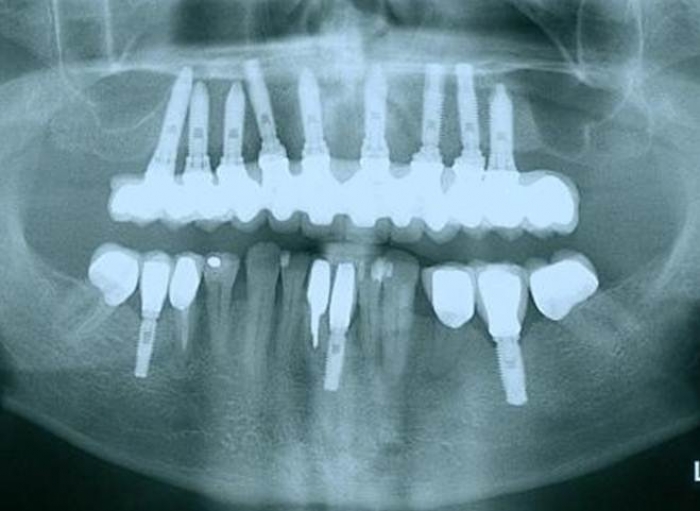

Raio X dos implantes

Raio X da prótese fixa em porcelana superior